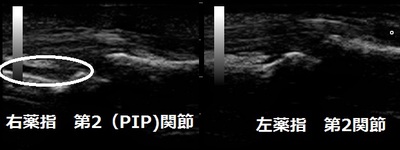

坂戸市 高校生 右手薬指の痛み ねんざ(掌側版損傷)。

右手薬指が腫れていて、曲げ伸ばしが痛くて出来ません。超音波検査では第2関節の掌側板(線維性軟骨で

過伸展を抑制)が損傷して内出血していることが認められました(画像丸の中)。

損傷部がスムーズに癒合するように整復しシーネ(添え木)で固定します。高校生は経過が良好で8日ほどで

固定を外しました。